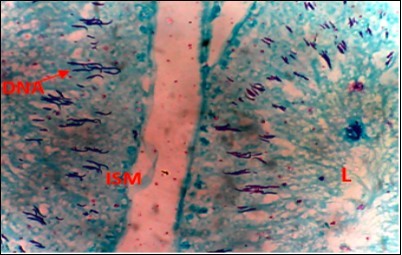

Local Nigerian men have been using AuriculariaPolytricha as a treatment for sexual dysfunction without supporting evidence from scientific experiments. This study was to investigate the effect of ethanolic extract of A. Polytricha on testicular DNA expression and some oxidative stress markers using STZ-Induced diabetic rats as a model. The experiment included six groups, Group A (Normal Control, treated with normal saline), Group B (treated with 65mg/kg.bw of STZ), Groups C, D, and E (treated with 250mg/kg.bw, 500mg/kg.bw, 1000mg/kg.bw AP after inducing diabetics), and Group F (treated with 40mg/kg.bw metformin after inducing diabetics). The experiment lasted for 35 days. After termination of the experiment, Fuelgen nuclear reaction was used for DNA demonstration to assess testicular DNA distribution while serum Superoxide Dimutase (SOD), Catalase and Melondialdehyde where evaluated using reagent based antioxidant enzyme assay. Results reveals that SOD and Melondialdehyde activities were remarkably (p<0.05) higher in diabetic control animals when compared with the normal control group. Values in Groups C, D and F that were administered with 250, 500mg/kg.bw A. polytricha and metformin respectively were also significantly (p<0.05) increased when compared with the normal control group. However, diabetic animals placed on 1000mg/kg.bw A. polytrichadid not show any statistical significance in comparison with normal control group but was remarkably (p<0.01) decreased when compared to the diabetic group that received low dose A. polytricha, an indication that the reversal is dose dependent. Catalase concentration in diabetic control animals was remarkably (p<0.05) higher when compared to the normal control but was not significantly (p<0.05) different in groups D (DM+500mg/kg.bw A. polytricha) and E (DM+1000mg/kg.bw A. polytricha) when compared with the normal control group. Diabetic control animals showed reduced magenta colour intensity of DNA and increased clustering and cross linking of DNA strands when compared with the normal control. However the degree of cross link in DNA strands was reduced in the diabetic animals placed on 1000mg/kg.bw A. polytrichawhen compared with the diabetic control group. Reversal in DNA damage and values of serum oxidative stress markers following administration of graded doses of A. polytricha could be attributed to essential phytochemical and therapeutic constituents in A. polytricha like polyphenol and flavonoid which can be found useful in prevention and treatment of diabetes induced testicular dysfunction. In summary, AP can contribute to a reversal in DNA damage and levels of serum oxidative stress markers in treating diabetes-induced testicular dysfunction.

Oxidative stress markers (SOD, catalase and Melondialdehyde) activities of different experimental animals. Figure 1, Figure 2. Results from Fuelgen DNA demonstration is shown in Figure 3, Figure 4, Figure 5, Figure 6, Figure 7, Figure 8.

Figure 7.(DC+1000mg/kg.bw of AP) X400 – Section of testis showing scanty DNA deeply stained with magenta color. DNA strands has reduced clusters

From findings in this study, irregular and distorted arrangements of DNA in all diabetic groups (Groups B, C, D, E and F) when compared with the normal control group, may have been due to displacement of sertoli cell within the germinal epithelium of seminiferous tubules. Strands of DNA were also seen arrange in clusters in diabetic groups, showing altered and defective structure which might have resulted from base free side deletion, frame shift, cross-linking and chromosomal rearrangement. The intensity of magenta colour development in Feulgen reaction for DNA demonstration was proportional to DNA concentration. There was reduced colour intensity in all diabetic groups (Groups B, C, D, E and F) when compared with the normal control. This is in line with report from Aitken and Krausz (2001). However the degree of distortion and cross-linking of DNA strand in the group of diabetic animal models placed on high dose (1000mg/kg.bw) of A. polytricha which may be a sign of amelioration. Groups C, D and F placed on 250mg/kg.bw A. polytricha, 500mg/kg.bw A. polytricha and standard anti-diabetic drug (metformin) respectively did not show remarkable differences in terms of DNA arrangements when compared with the diabetic control group. Groups D (500mg/kg.bw A. polytricha) and group E (1000mg/kg.bw) showed visible improvement in magenta colour intensity when compared with the diabetic control group.

The marginal reversal of DNA damage following 21 days of A. polytricha administration, as observed in this study may be linked to its polysaccharides constituent found to exhibit antimutagenic effect against in-vivo DNA damaging activities of indirectly acting alkylating agent. A. polytricha may have improved antioxidant status of experimental animals and was capable of ameliorating DNA damage which may be attributed to its potentials to regulate concentration of carboxymethyllysine (CML) and advanced glycation end (AGE) which are important triggers of oxidative stress in the reproductive tract of diabetic animals. AP is known to be a good exogenous source of antioxidant and may have ameliorated further DNA damage.